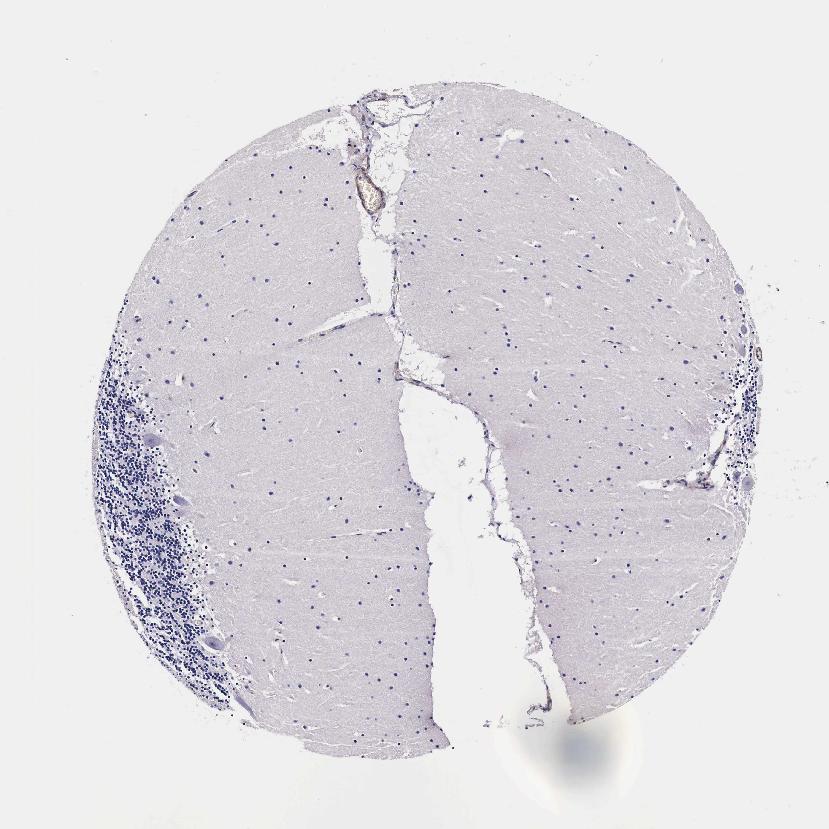

CEREBELLUM - Antibody stainingi

Antibody staining in the annotated cell types in the current human tissue is reported as not detected, low, medium, or high, based on conventional immunohistochemistry profiling in selected tissues. This score is based on the combination of the staining intensity and fraction of stained cells.

Each image is clickable and will lead to virtual microscopy that enables deeper exploration of all samples and also displays staining intensity scores, fraction scores and subcellular localization as well as patient and tissue information for each sample.

Antibody HPA000497Antibody CAB004439Antibody CAB047331

Purkinje cells Not detectedMedium-

Purkinje cells - cytoplasm/membrane --Medium

Purkinje cells - dendrites --Medium

Purkinje cells - nucleus --Not detected